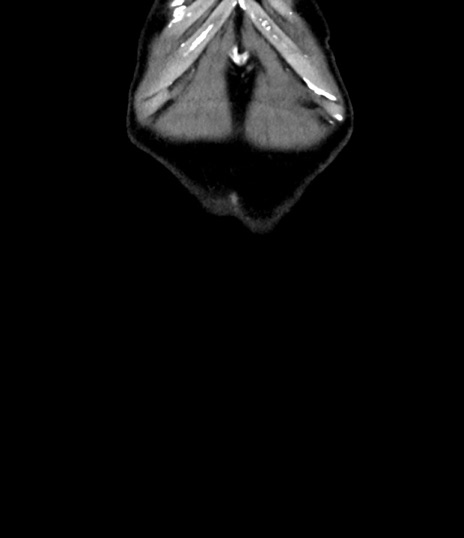

横断像

【症例】 60歳代男性

【主訴】 黒色吐物

【現病歴】 4日前から嘔気自覚、2日前の朝食後にも嘔気あり、自分で手で嘔吐反射起こし嘔吐したところ血が混ざっていたため受診。

【既往歴】 5年前汎発性腹膜炎を伴う急性虫垂炎で手術、高血圧、前立腺肥大症、高脂血症

【身体所見】 腹部正中に手術癩痕あり 腹部平坦・軟圧痛なし膨満感あり

【データ】WBC 8400、CRP 4.54